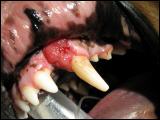

Max ist ein 10 Jahre alter Golden Retriever, der bei uns in der Praxis 2005 wegen eines Geschwüres im Oberkiefer vorgestellt wurde.

Das Ergebnis war leider erschreckend, da es sich um einen bösartigen Tumor handelte, welcher so schnell wie möglich entfernt werden musste. Max bekam einen Termin zur Operation.

Max: Tumor